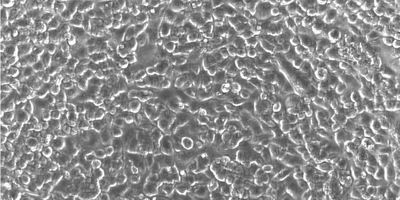

This new tool could help unlock the medicinal value of millions of archived cancer samples